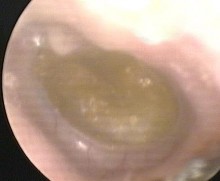

Hình ảnh nội soi tai

Ảnh 6 MN có mức dịch MSBA. 1811255336 |

Ảnh 8 MN lõm, vàng MSBA. 1912331936 | |

Ảnh 9 MN lõm, xanh MSBA. 1806217636 |

Ảnh 10 MN xẹp chưa chạm vào ụ nhô MSBA. 1806217633 |

Ảnh 11 MN xẹp chạm vào khớp đe đạp MSBA. 1806217173 |

Ảnh 12 MN dính vào ụ nhô, khớp đe đạp MSBA. 1901263977 |